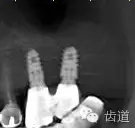

6、45,46,47牙片

7、45,46,47CBCT